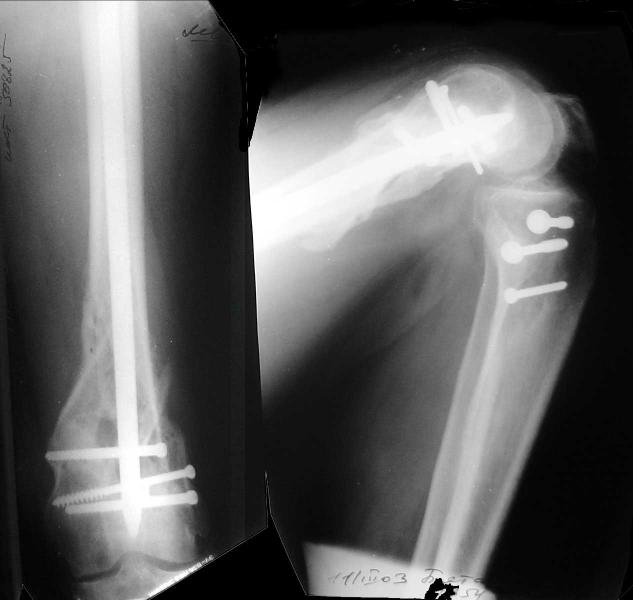

This is what we have done... As generally true for LISS look at the bone not the hardware.

There are two more srews above. The one not completely in got damaged head.

Zsolt